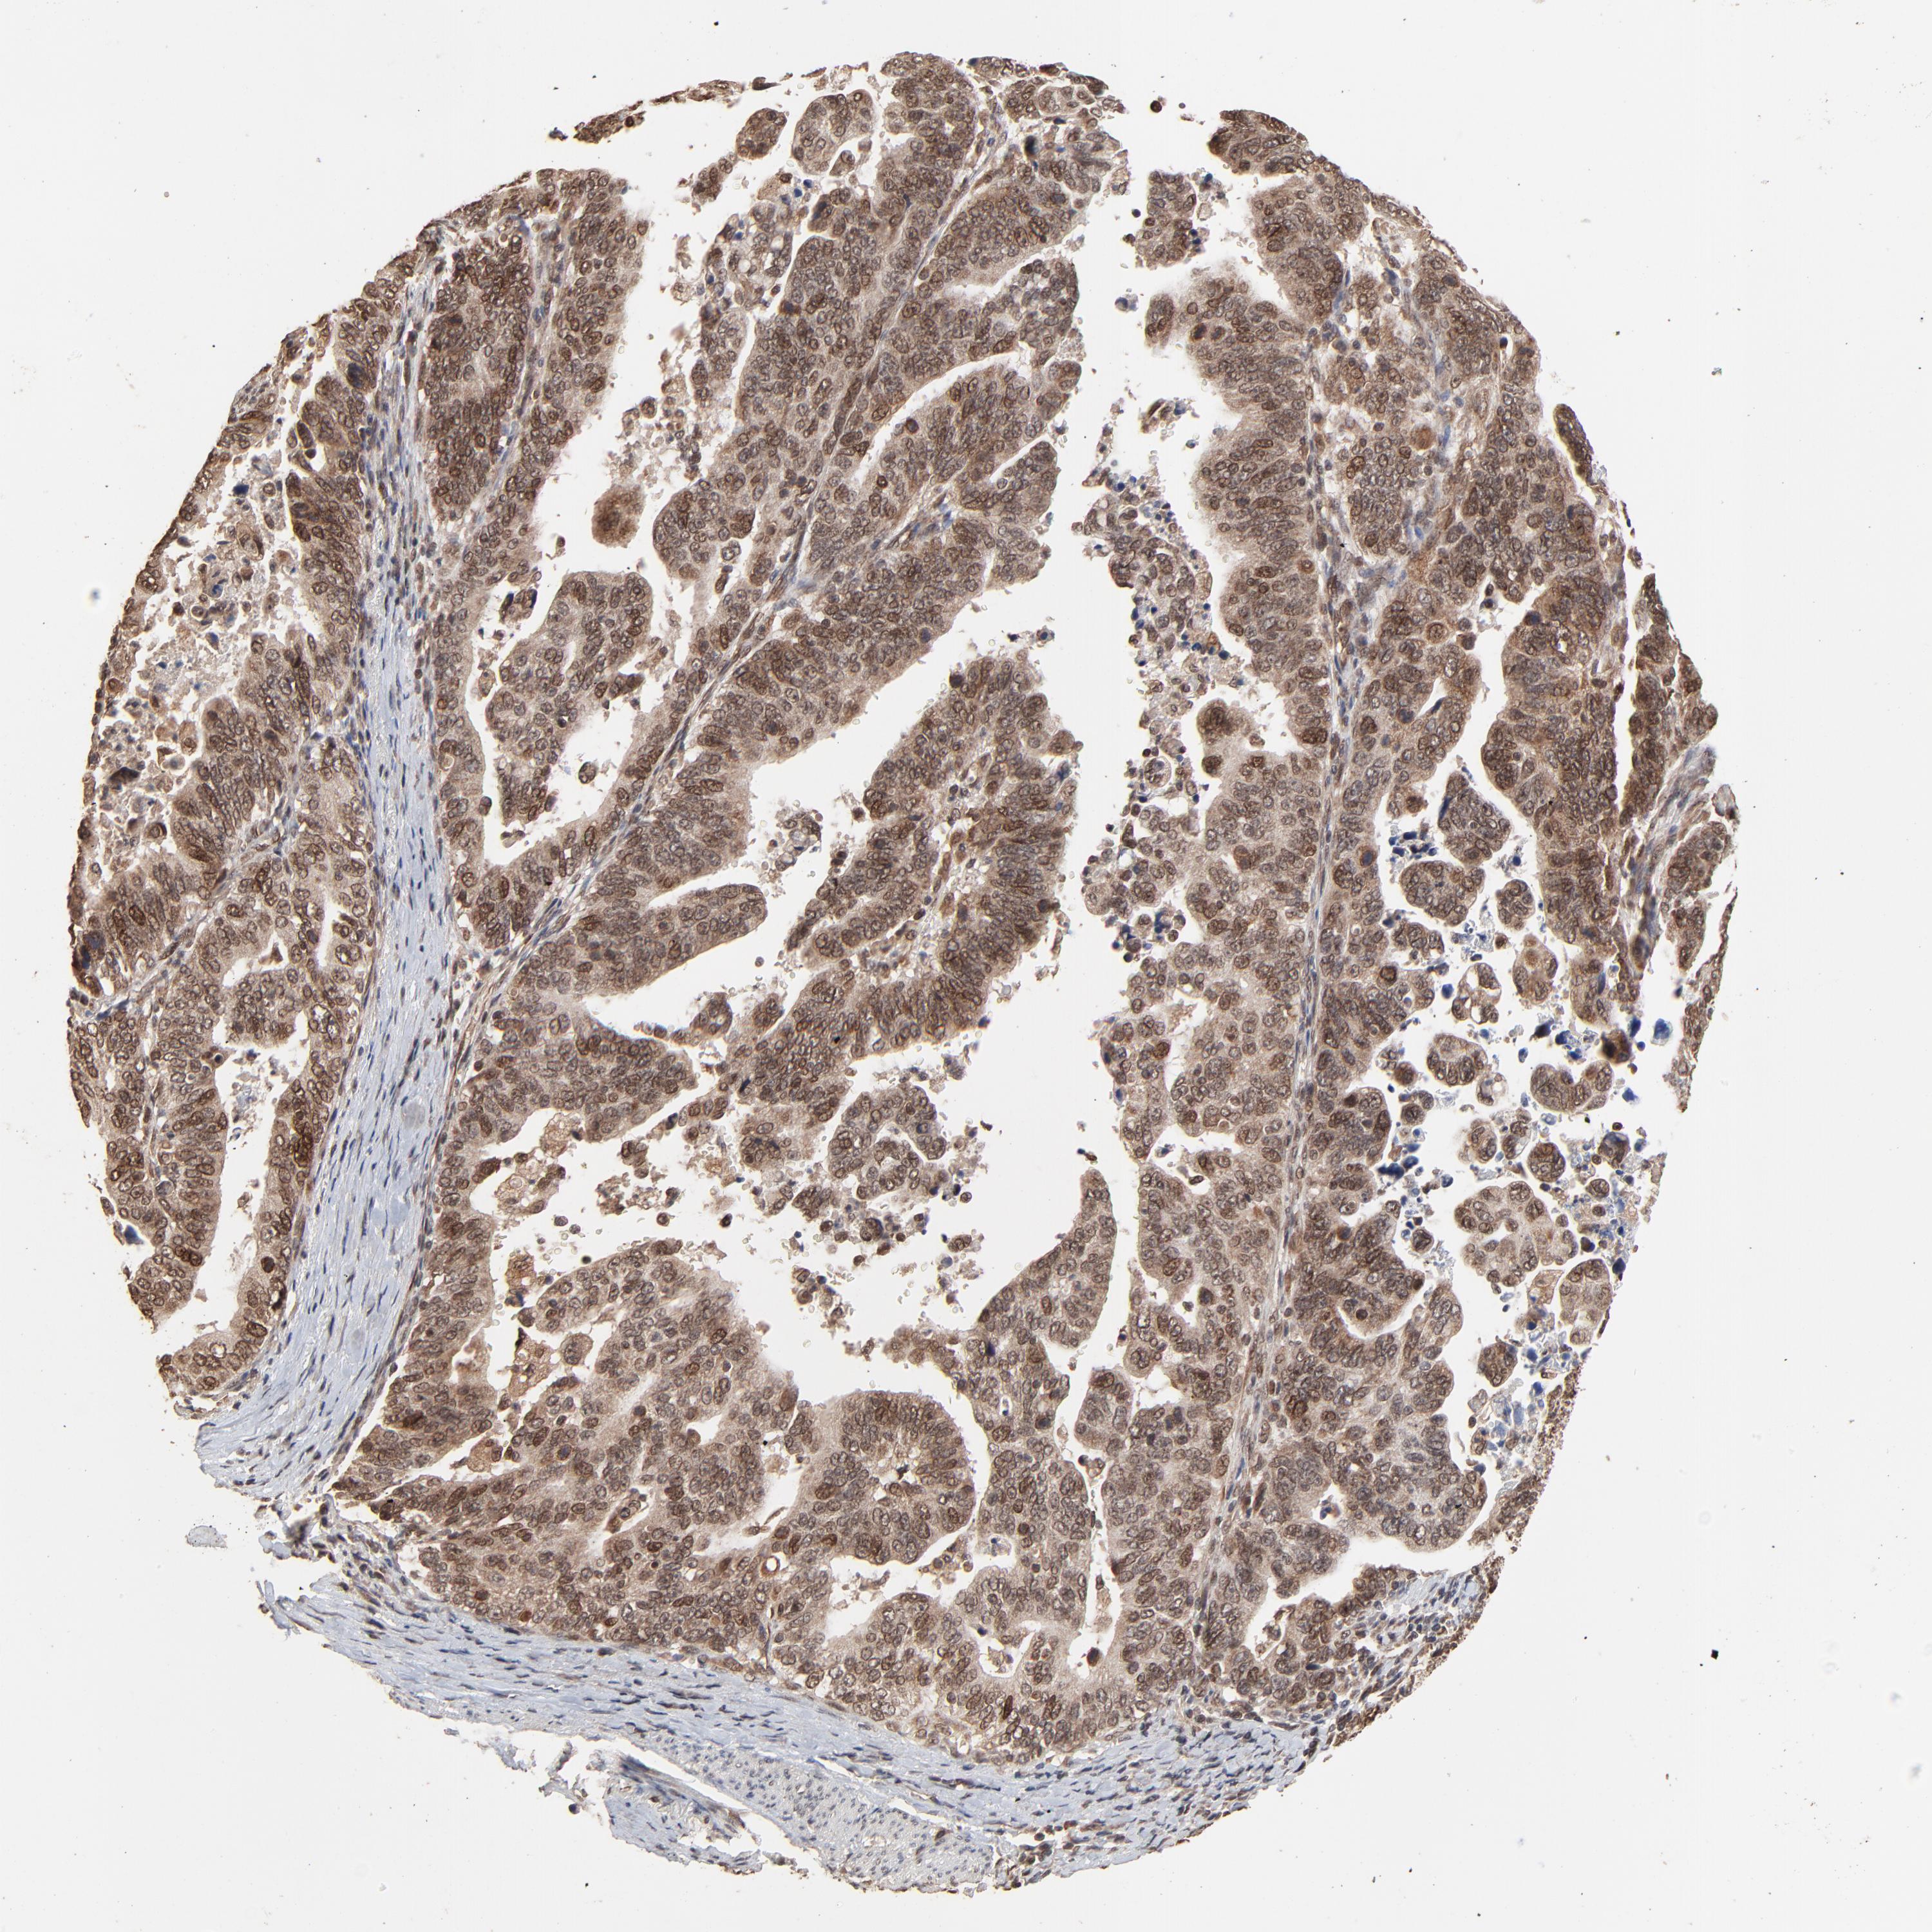

STOMACH CANCER - Protein expressioni

A mouse-over function shows sample information and annotation data. Click on an image to view it in a full screen mode. Samples can be filtered based on level of antibody staining by selecting one or several of the following categories: high, medium, low and not detected. The assay and annotation is described here.

Note that samples used for immunohistochemistry by the Human Protein Atlas do not correspond to samples in the TCGA dataset.

Antibody stainingi

Antibody staining in the annotated cell types in the current human tissue is reported as not detected, low, medium, or high, based on conventional immunohistochemistry profiling in selected tissues. This score is based on the combination of the staining intensity and fraction of stained cells.

Each image is clickable and will lead to virtual microscopy that enables deeper exploration of all samples and also displays staining intensity scores, fraction scores and subcellular localization as well as patient and tissue information for each sample.

Antibody HPA003077

Staining

High

Medium

Low

Not detected

Intensity

Strong

Moderate

Weak

Negative

Quantity

>75%

75%-25%

<25%

None

Location

Nuclear

Cytoplasmic/membranous

Cytoplasmic/membranous,nuclear

Adenocarcinoma, NOS